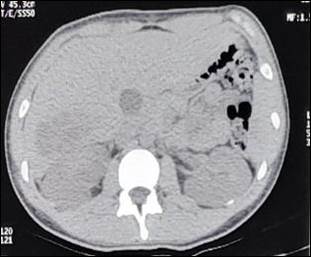

Se trata de un masculino de 17 años sin antecedentes que refiera. Acude derivado de otra institución por presentar cuadro clínico de 5 días de evolución por fiebre asociado a dolor lumbar derecho, que se presentó posterior a caída de su propia altura. Se realizó laboratorios donde presentó leucocitosis (Glóbulos blancos 14 mil/mm3) con predominio de neutrófilos (Neutrófilos 84%), cultivos periféricos, ecografía abdominal completa que mostró una imagen hipoecoica en polo superior de riñón derecho, urotomografía simple que mostró imagen hipodensa heterogénea compatible con absceso renal (Figura 1), ante lo cual se decide tratamiento antibiótico endovenoso con ceftriaxona y amikacina endovenosa.

Ilustración 1 UROTOMOGRAFÍA SIMPLE

Figura 1: Urotomografía. A) Simple: Se evidencia imagen hipodensa en polo superior de riñón derecho que se correlaciona con imagen hipodensa a nivel de lóbulo hepático derecho. B) Contrastado: En el segmento VI del lóbulo hepático derecho se evidencia una lesión ocupativa hipodensa tabicada con realce capsular periférico que mide 6,5 x 5 cm., está en contacto con el riñón, incluso en el parénquima renal se demuestra un área focal mediamente hipondesa compatible con absceso hepático con afectación al parénquima renal.